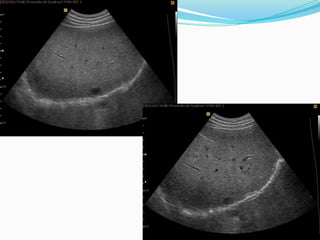

IMAGEN PARAMEDIANA LONGITUDINAL DERECHA

IMAGEN TRANSVERSAL, MEDIOABDOMINAL DERECHA